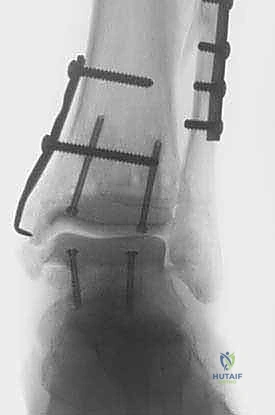

- في بعض الحالات المعقدة، قد يتطلب الأمر إجراء قص عظمي في الكعب (Malleolar Osteotomy) لفتح المفصل بالكامل ورؤية السطح المتضرر بوضوح، ثم يتم إعادة تثبيت هذا العظم لاحقاً.

4. زراعة الطعم وتثبيته (Graft Implantation and Fixation)

- يتم تشكيل الطعم المأخوذ من المتبرع ليطابق الحفرة التي تم إعدادها في كاحل المريض تماماً (مثل تركيب قطعة البازل).

- يتم إدخال الطعم برفق (Press-fit).

- لضمان الثبات التام، يتم تثبيت الطعم باستخدام براغي دقيقة جداً (غالباً تكون قابلة للامتصاص البيولوجي أو براغي تيتانيوم غاطسة تحت مستوى الغضروف حتى لا تحتك بالمفصل).

صور إضافية من داخل غرفة العمليات والخطوات الجراحية

ندرك أهمية توثيق الخطوات الجراحية لطلاب الطب والمرضى الراغبين في فهم دقة الإجراء. هذه الصور توضح مراحل زراعة وتثبيت الطعم العظمي الغضروفي بدقة متناهية تحت إشراف أ.د. محمد هطيف.